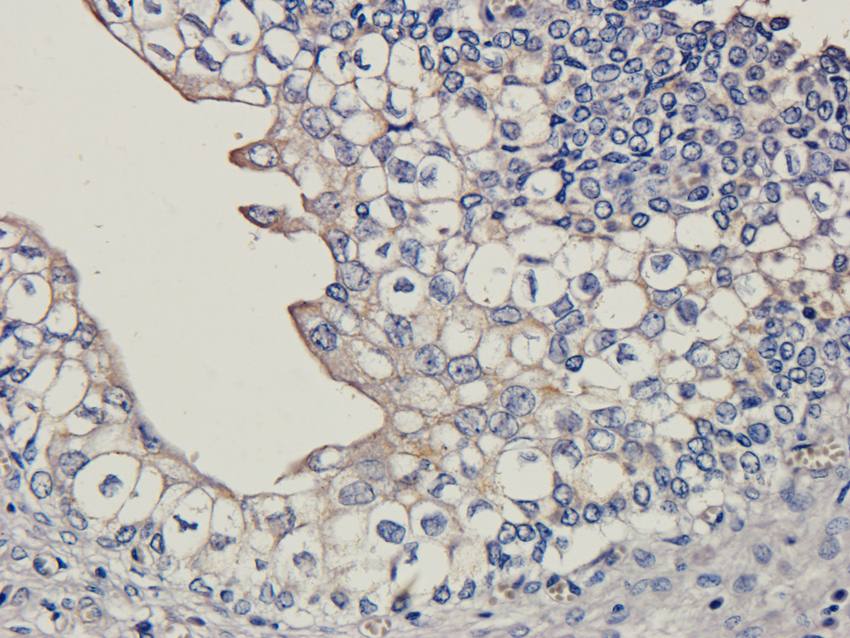

应用稀释比例:IF/ICC: 1:50-400, WB: 1:200-1000, IHC-P: 1:50-400